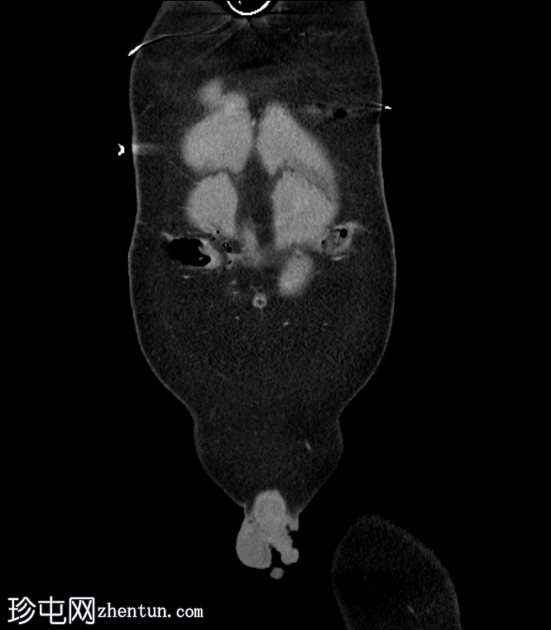

冠状位增强扫描(门静脉期)

气腹伴复杂性腹膜积液,提示全层肠损伤。

前腹壁多处刺伤,横结肠和肠系膜经右侧和左侧腹直肌鞘中部疝出。

左侧后方分层血胸。